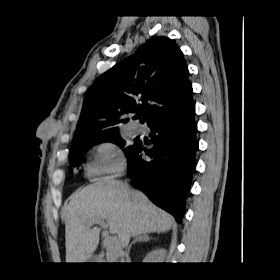

A 62 years old man with enlarged mole on chest since 2 months.

CT chest :-